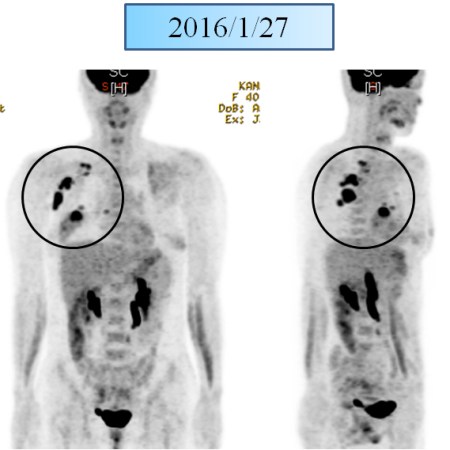

유방암 11강 – 수술 후 tamoxifen을 사용한 소양인 유방암 환자 이야기

유방암 10강 – 유방암3기 – 양방치료를 거부한 소양인 유방암 환자이야기 – 양측성 종양과 겨드랑이 림프절 전이